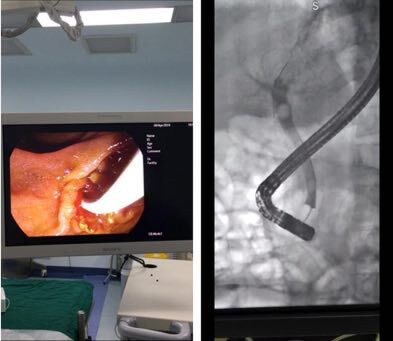

终于,赖大叔经朋友推荐,来到深圳光明的中山七院就诊。汤地主任组织普外科团队评估他的病情后,衡量利弊,为他推荐了一个治疗方案——“通过十二指肠镜、腹腔镜、胆道镜三种内镜设备,用微创手术去除胆结石。”

通过这三面镜子的完美配合,无死角“照亮”胆道系统,可以清晰观察胆道内部情况,发挥各自的优点,帮助医生精准取出胆结石,保护胆道系统不受破坏。

“三镜联合的胆结石手术治疗可达到全程微创、直视取石、自然腔道引流、保留胆道括约肌功能,胆总管无须放置T管的效果,大大减轻了病人痛苦,提高了治疗疗效,同时术后胆漏、结石复发率也最低。”普外科汤地主任介绍道。

综合各种治疗方法利弊后,汤地教授团队为患者制定了三镜联合取石治疗的方案:首先行十二指肠镜下经十二指肠胆道造影术(ERCP)+鼻胆管引流术(ENBD),ERCP术中不进行十二指肠乳头切开。

这种特有的解剖结构和功能特点非常有利于内镜的诊断和治疗。ERCP(经内镜逆行胰胆管造影术)可通过人体自然腔道运用十二指肠镜实施胆胰管造影及相关治疗(如活检、取石、碎石、支架植入、鼻胆管引流等),在当代胆胰疾病诊治中发展迅速,优点包括:不用开刀、创伤小、恢复快。

但是,ERCP碎石、取石过程中如果切开乳头范围过大,有可能破坏胆道门户,引起反流性胆管炎和胆总管结石的迅速复发。因此,ERCP属于高级内镜技术,技术难度高,目前能够顺利开展的医院不多。